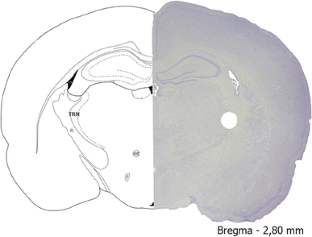

Fig. 1